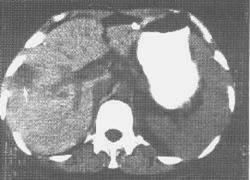

7.CT掃描

能發現肝內病灶。